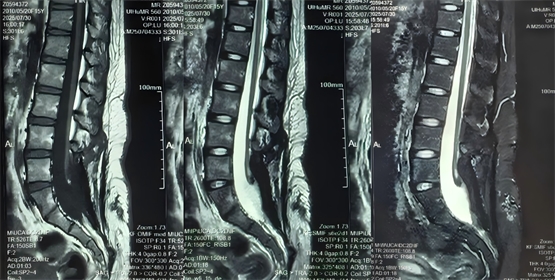

為尋求進(jìn)一步診治,患者再次來(lái)到我科就診,入院后,李萃萃主任團(tuán)隊(duì)為患者進(jìn)行了全面的檢查和評(píng)估,診斷為“脊髓拴系術(shù)后、脊柱裂、神經(jīng)源性膀胱、神經(jīng)源性直腸”。結(jié)合患者脊髓拴系術(shù)后遺留大小便失禁的情況,決定為患者行“骶神經(jīng)調(diào)控手術(shù)”。

圖2為此次手術(shù)前復(fù)查腰骶椎MR檢查,提示脊髓拴系松解滿(mǎn)意